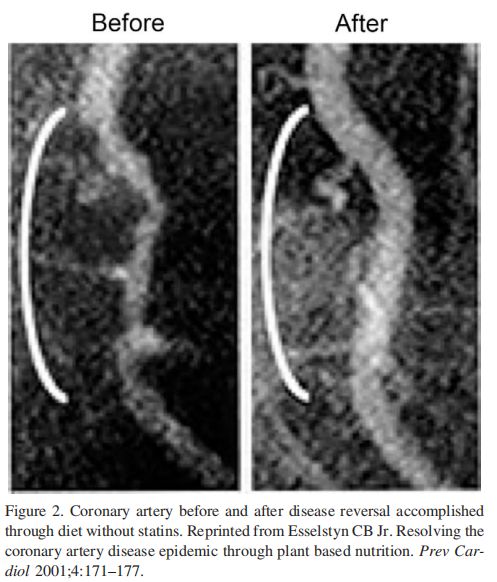

生活方式能否预防和逆转相关富贵病呢?埃塞斯廷(Caldwell Esselstyn)医生过去30年用基于无油烹饪的低脂全蔬食逆转了200案例的心血管疾病。

1985年我开始从事一项研究, 采用蔬食营养治疗患有严重冠心病的病人,成功地控制和治愈了他们的病情。这一课题已公开报道了5年期15、12年期16、16年期17的研究结果,最近总结的为期20年的研究成果已发表在我的著作中,其书名为《预防和逆转心脏病》,18 它是同类医学研究中为期最长的调查项目之一。研究期的持续证明了冠心病病人将会坚持吃这些新改变的饮食长达数十年, 甚至更长。结果是病人的体重下降、血压转为正常,以及2型糖尿病好转或逆转, 心绞痛、阳痿、以及外周血管和颈动脉疾病也得到改善或治愈;他们的血管造影结果明显改善。更为了不起的是,当谈到制止和治愈他们的疾病时,患者所赢得的那种自我掌控感。